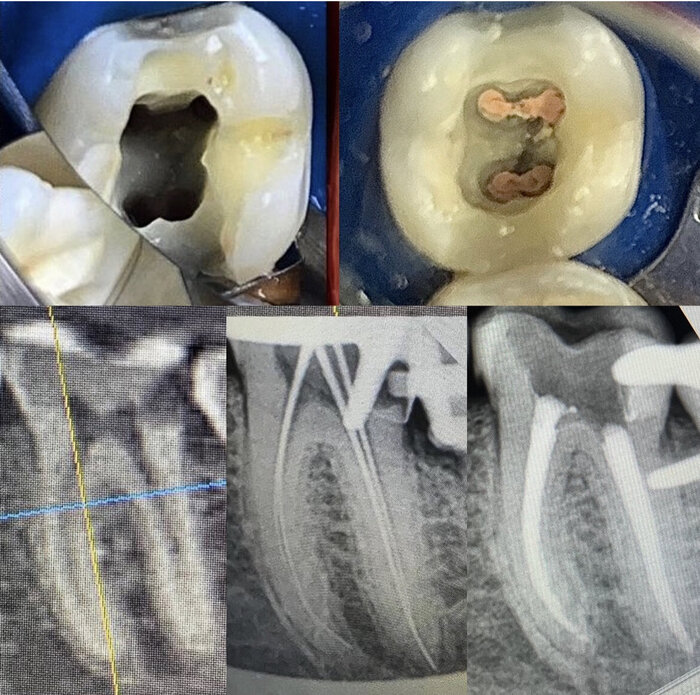

Мне всё рассверлили, спросили, ачё ачё, сказали - сча починим и всё збс. Ну, я это и хочу, аллилуйя! Но потом она смотрит смурно - нужен снимок. Лан. Идём делаем снимок. Нет времени, ты прибежал внезапно, сча клиенты, въебём мышьяка по старинке и приходи послезавтра. Потом ещё через 4 дня придёшь за финальной пломбой и ходи безпульпитный и щасливый! Да нивапрос, лишь бы не ебало меня поперёк жизни этой болью. Отдал тыщу и ушоль. Прихожу через два дня - там всё сверлят, суют микроиголочки, цокают, делают три снимка "ну тут всё хорошо с каналами, давай 4 тыщи", ставят времянку и отправляют домой, чота нитак у тебя - через 4 дня придёшь, а потом через день - финал. Ну... Ок.

Прихожу через 4 дня - рассверлили, потыкали всякими желесками - чота нито. Пойдём делать снимки. Сделали 4 снимка с разными штифтами (потом в фактуре прочитал, такта я и не знал бы, иголочки и иголочки) "ну такта всё нормально, поставим вам гуттаперчевые штифты и всё збс буит, дайте 5 тыщ" и идите, завтра придёте и всё. Нуууу, ок. Ухожу. Прихожу. "Ну тут чтота нипанятное, давайте сделаем фото ещё, штук 5. О, ну каналы чистые, зря снимали. Но у вас тут десна воспалилась, давайте послезавтра, с вас 3 тыщи". Ээээ.... Какой-то неприятный осадок нарастает. Говорю, мол, вы мне объясните, почему вы сказали, что за 3 раза всё тут ̶р̶а̶з̶ъ̶е̶б̶ё̶т̶е̶ почините и вернёте как было (а все же знаю, как сделать охуенно русскому человеку - сделай ему хуёво и верни как было, счастья через край), а верёвочка всё вьётся, и петли в конце не видать. Пачиму???

И вот тут затык. Ну, у вас кровило. Ну, у вас каналы узенькие. Нипанятна. Ну, времени между клиентами не хватило. Ну, вы же сказали больновато - поставили снова укол. Ну чот странно выглядело. И вот я уже 6 раз сходил. И ещё вроде на пару раз. И уже далеко не 10 тыщ. Но куда мне деваться? Вроде непонятно. Вроде чота нитак. Вроде кровит. И всё бы ок. Но после 8-го подряд снимка "ну тут всё нормально, зря переживали", стали возникать вопросики - а хули там могло измениться за неделю??? Каждый раз по два снимка... Да мож оно так и надо, я бы даж против не был! Вы просто сразу расскажите обо всех подводных камнях, пжалста!